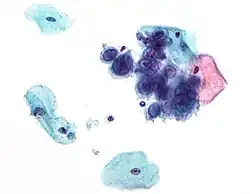

Placentitis por citomegalovirus (CMV)

Placentitis por citomegalovirus (CMV) -

Placentitis por citomegalovirus (CMV)

Placentitis por citomegalovirus (CMV)

Si la madre tiene herpes simplex activo (como lo puede sugerir una prueba de Papanicolaou), el parto por cesárea puede evitar que el recién nacido entre en contacto y, en consecuencia, se infecte con este virus.